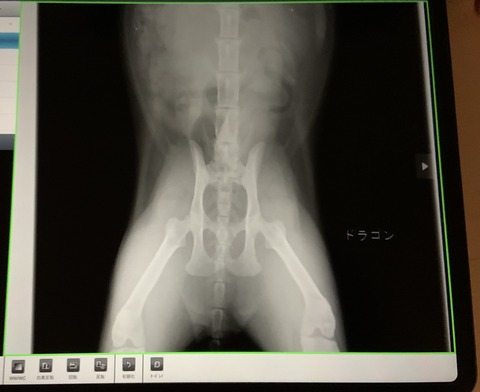

エコーとレントゲンの結果、尿管閉塞を起こすような石はできていないことが

確認できたので、少し安心しました

▼レントゲン